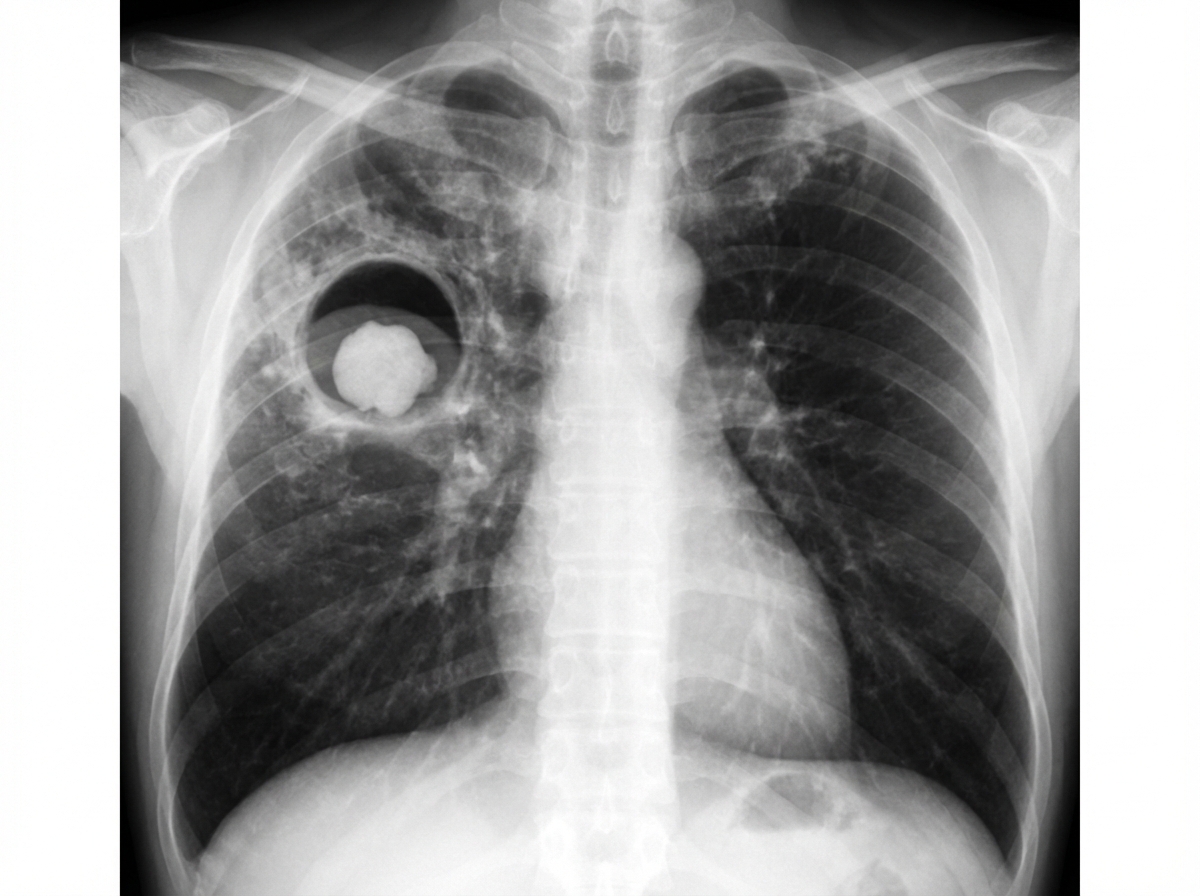

A 48-year-old man comes to the physician because of a 1-month history of a productive cough. He has daily yellowish sputum with occasional streaks of blood in it. Twelve years ago, he was treated for pulmonary tuberculosis for 6 months. He has hypertension and coronary artery disease. He does not smoke or drink alcohol. Current medications include metoprolol, clopidogrel, rosuvastatin, and enalapril. He appears thin. His temperature is 37.2°C (99°F), pulse is 98/min, and blood pressure is 138/92 mm Hg. Pulmonary examination shows inspiratory crackles at the right infraclavicular area. His hemoglobin concentration is 12.2 g/dL, leukocyte count is 11,300/mm3, and erythrocyte sedimentation rate is 38 mm/h. Urinalysis is normal. An x-ray of his chest is shown. Which of the following is most likely to be seen on further evaluation of the patient?